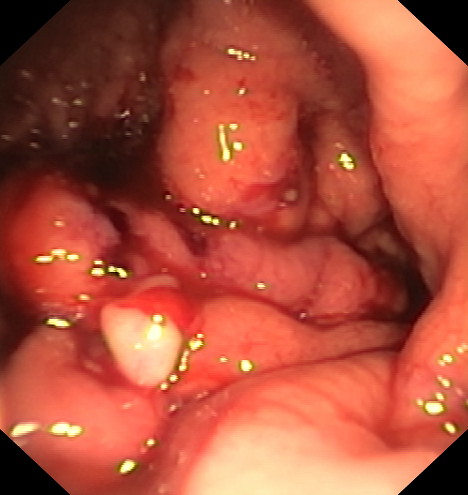

La gastroplastia endoscópica mediante la técnica endomanga se realiza por el gastroscopia, bajo anestesia general y dura aproximadamente entre 25 y 35 minutos. Mediante la endoscopia se realizan unos 18 pliegues definitivos a lo largo de todo el cuerpo gástrico, reduciendo de manera importante su capacidad de apertura, acortándolo y estrechándolo. Gracias a esta reducción los pacientes disminuyen la sensación de hambre.